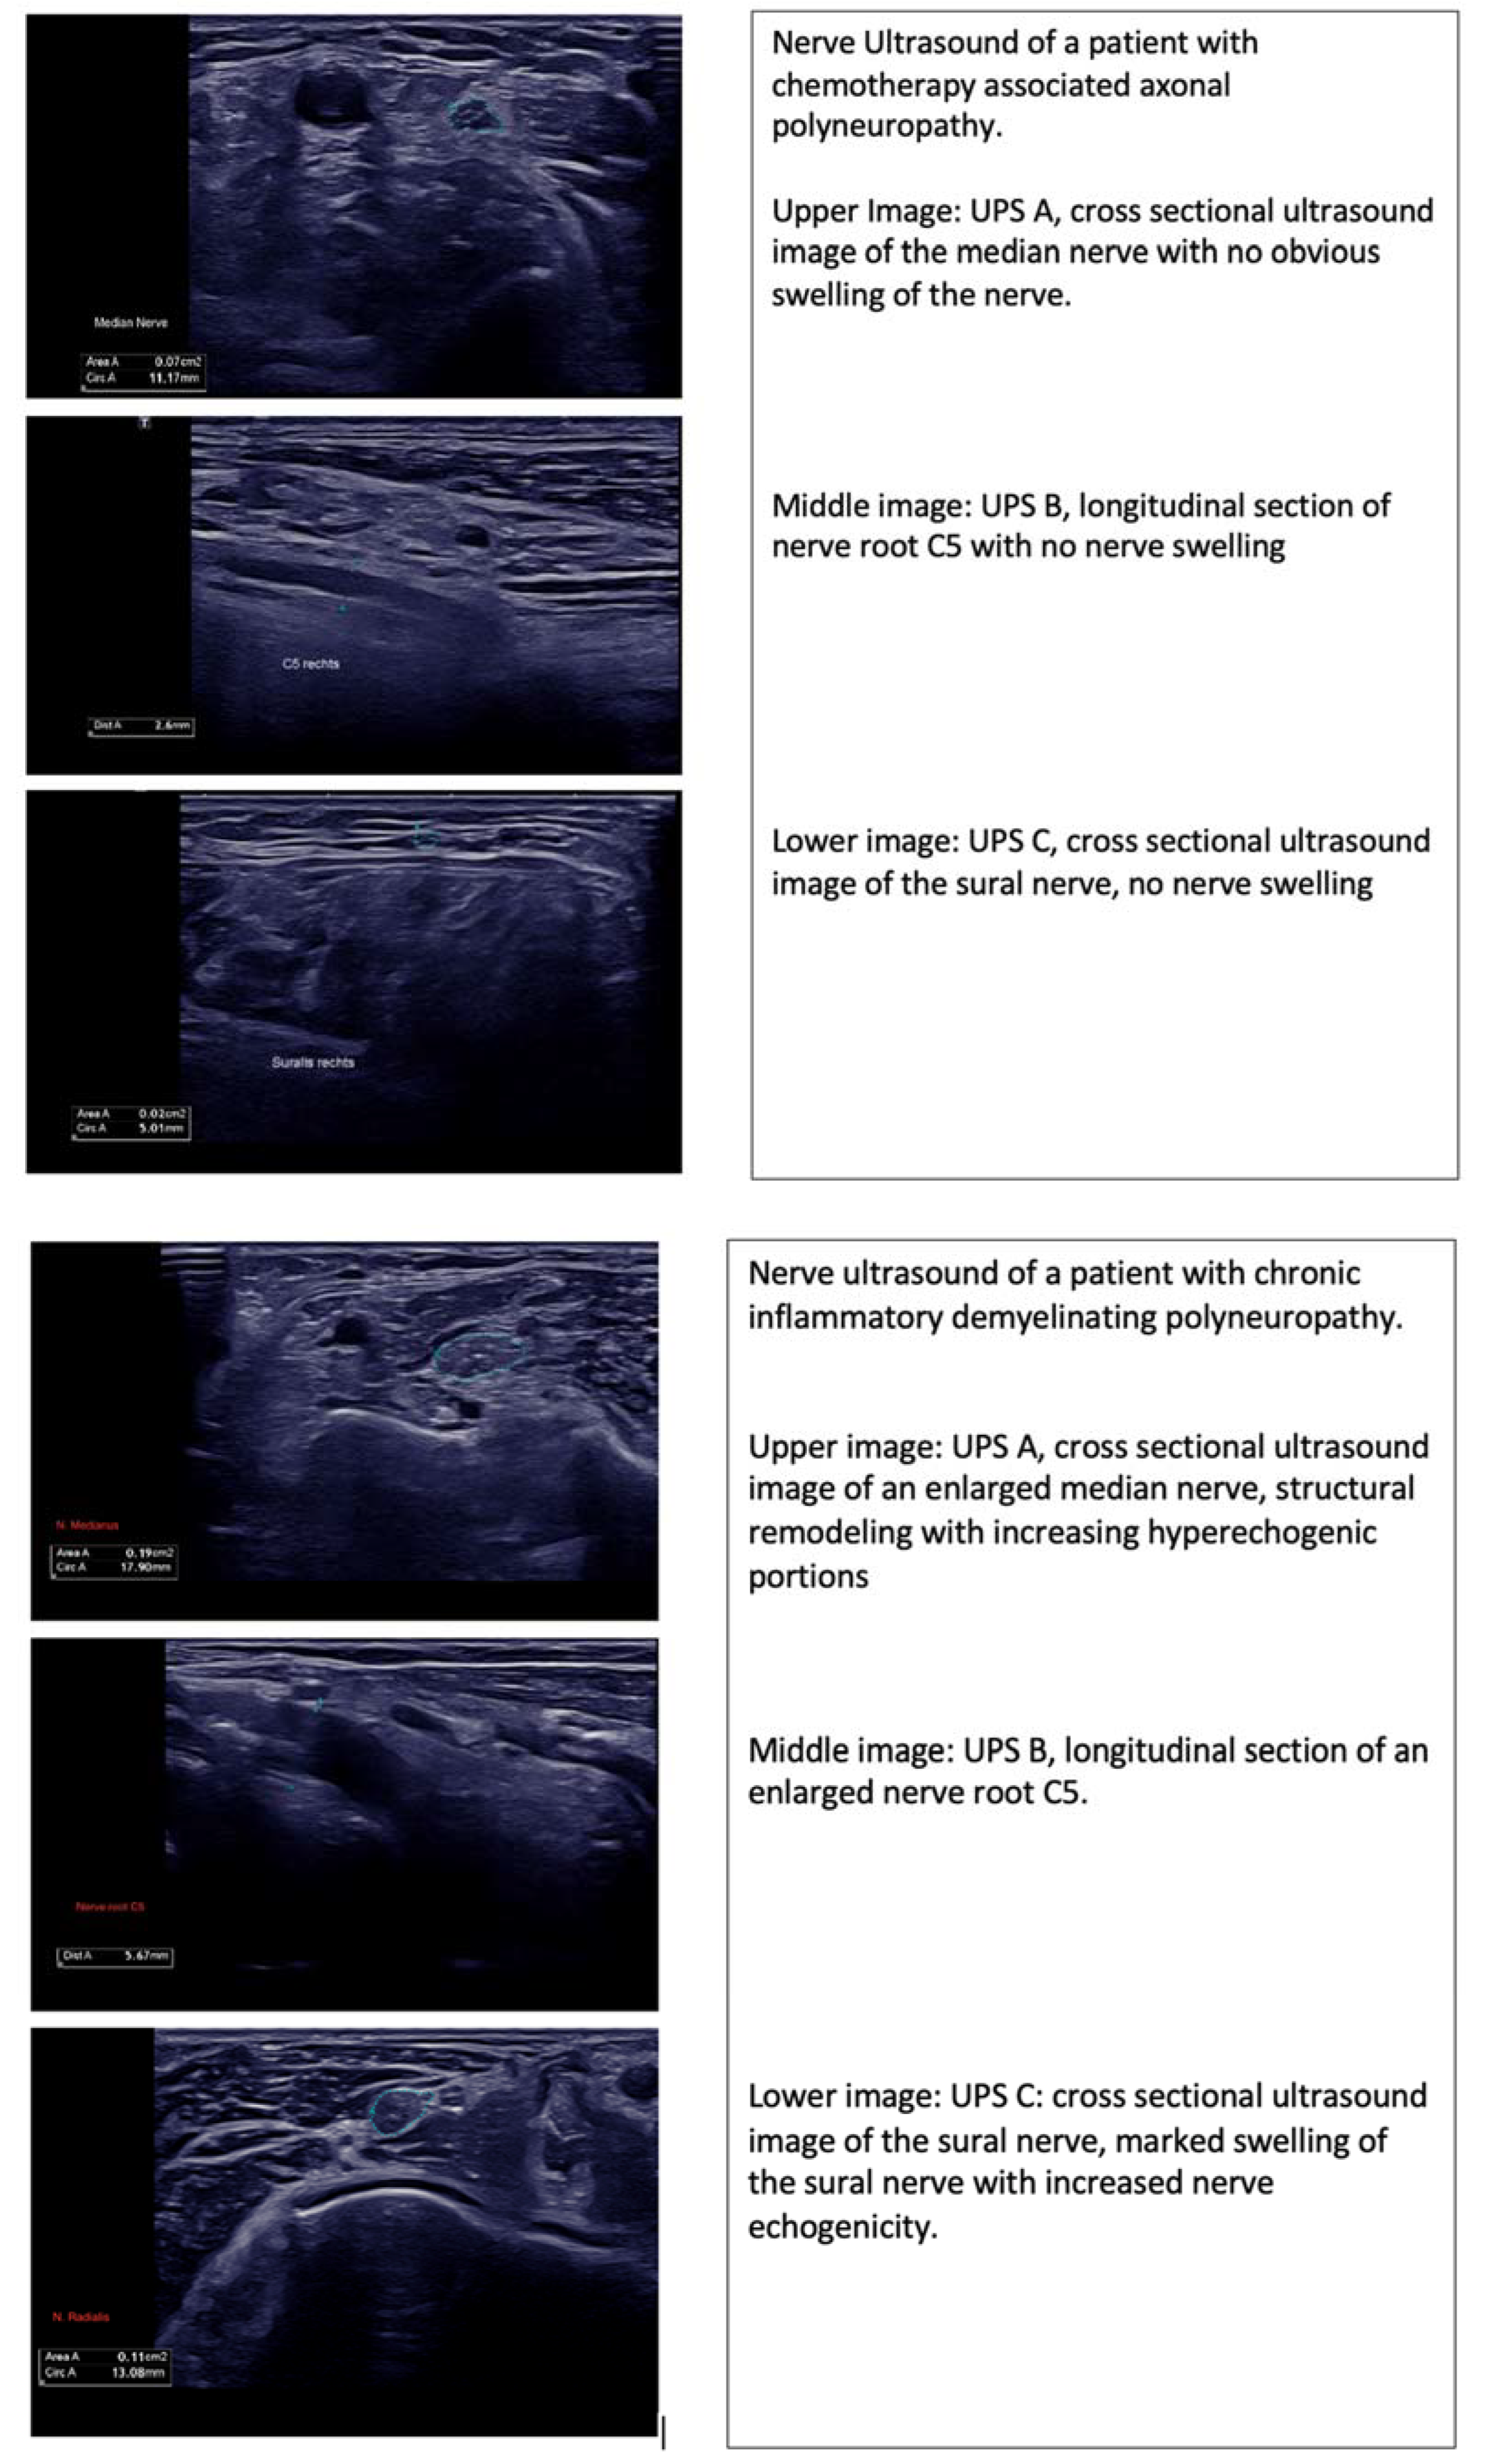

| 1 | 77 | M | Melanoma | Ipilimumab/Nivolumab | 5 UPS A 2 UPS B 2 UPS C 1 | Inconclusive | N/A | N/A | N/A |

| 2 | 56 | M | Small-cell lung carcinoma | Atezolizumab | 2 UPS A 0 UPS B 2 UPS C 0 | Axonal PNP | 10/µL cells, 156 mg/dL protein | IVIG | Negative |

| 3 | 53 | F | Melanoma | Atezolizumab | N/A | Axonal PNP | N/A | N/A | N/A |

| 4 | 65 | F | Melanoma | Ipilimumab/ Nivolumab | 2 UPS A 1 UPS B 1 UPS C 0 | Axonal PNP | 19/µL cells, 100 mg/dL protein | CS | Negative |

| 5 | 55 | F | Melanoma | Ipilimumab/ Nivolumab | 2 UPS A 2 UPS B 0 UPS C 0 | Axonal PNP | 26/µL cells, 1117 mg/dL protein | IVIG | Negative |

| 6 | 78 | M | Aesthesioneuroblastoma | Nivolumab | N/A | Axonal PNP | 18/µL cells, 144 mg/dL protein | N/A | N/A |

| 7 | 79 | M | Melanoma | Nivolumab | 0 UPS A 2 UPS B 0 UPS C 0 | Axonal PNP | 9/µL cells, 40 mg/dL protein | CS | Negative |

| 8 | 86 | M | Urothelial Ca | Pembrolizumab | 3 UPS A 1 UPS B 2 UPS C 0 | Axonal PNP | 13/µL cells, 77 mg/dL protein | IVIG | Negative |

| 9 | 68 | M | Urothelial Ca | Pembrolizumab | 2 UPS A 2 UPS B 0 UPS C 0 | Axonal PNP | 9/µL cells, 32 mg/dL protein | IVIG | Negative |

| 10 | 58 | F | Melanoma | Ipilimumab/ Nivolumab | 0 UPS A 0 UPS B 0 UPS C 0 | Axonal PNP | 22/µL cells, 72 mg/dL protein | IVIG | N/A |